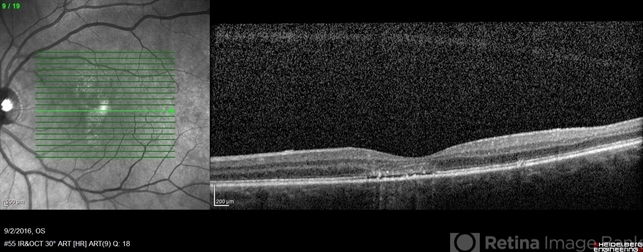

- placoid, maculopathy

- 68-year-old woman with decreased central vision over past few months following viral illness